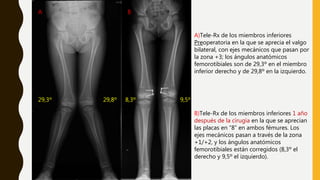

A)Tele-Rx de los miembros inferiores

Preoperatoria en la que se aprecia el valgo

bilateral, con ejes mecánicos que pasan por

la zona +3; los ángulos anatómicos

femorotibiales son de 29,3º en el miembro

inferior derecho y de 29,8º en la izquierdo.

A B

B)Tele-Rx de los miembros inferiores 1 año

después de la cirugía en la que se aprecian

las placas en “8” en ambos fémures. Los

ejes mecánicos pasan a través de la zona

+1/+2, y los ángulos anatómicos

femorotibiales están corregidos (8,3º el

derecho y 9,5º el izquierdo).

29,3º 29,8º 8,3º 9,5º